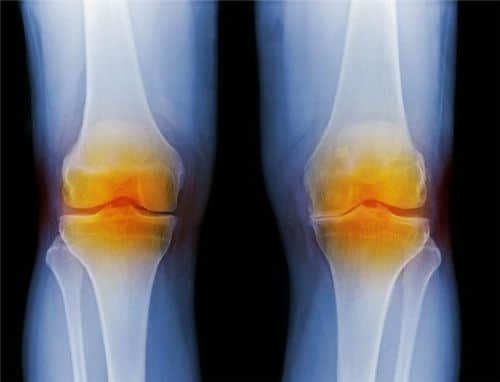

膝盖疼·到东坡 一家无需家属陪护的医院

当膝盖除了弹响,还伴有不适或疼痛时,应引起注意,膝盖内部组织可能出现问题。

建议及时休息,及时就医或寻求专业人士的帮助。